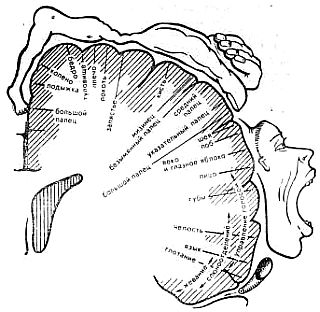

На рис. 7 показано поперечное сечение передней центральной извилины и черточками — площадь проекций каждой части тела. В самом низу находятся представительства (проекции) мышц губ, языка, гортани. Отсюда в заданной последовательности поступают импульсы на артикуляторные мышцы, и они начинают работать.

Рис. 7. Схема проекций различных частей тела в двигательной области коры головного мозга. Размер отрезков линии на схеме пропорционален размеру проекций частей тела в коре.